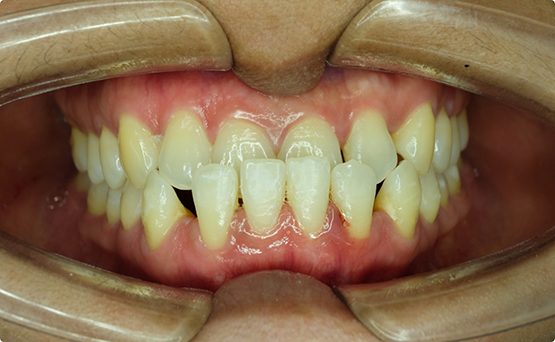

Case 2

Adult female, unilateral posterior crossbite, crowded upper arch, class II molar relation on the right with narrow smile on the right side.

Treatment: Patient was treated with an expander followed by Invisalign clear aligners.